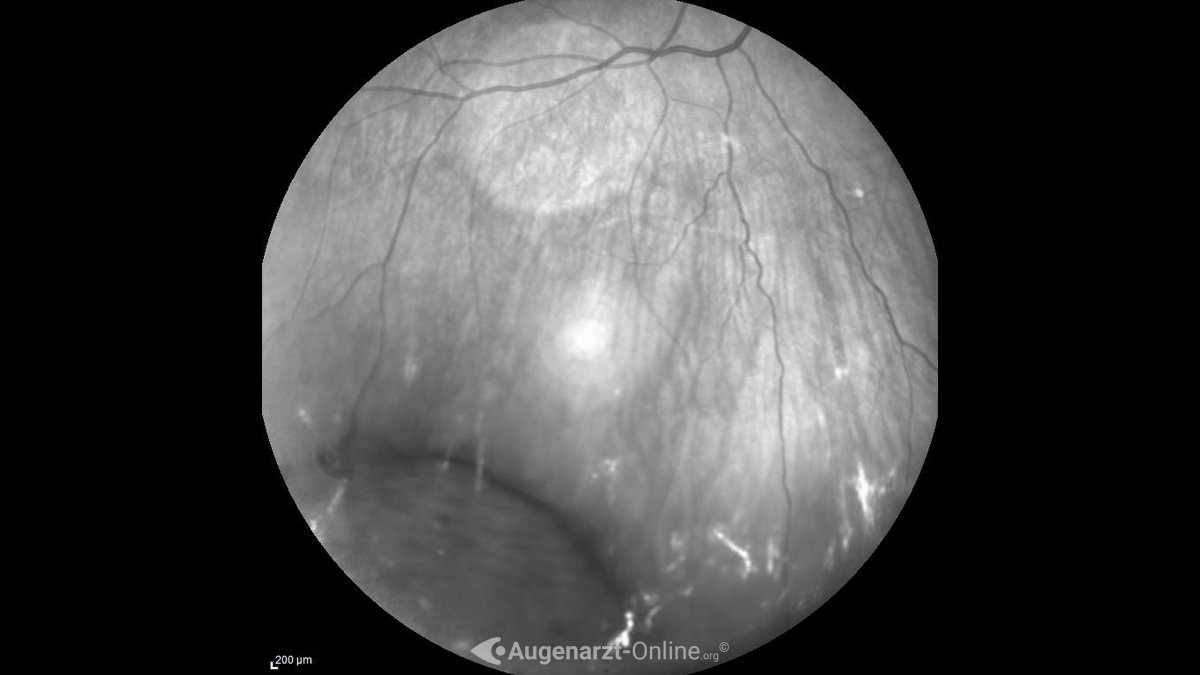

From www.augenarzt-online.org

Retinoschisis Atlas der Augenheilkunde Retinoschisis Is It can be degenerative or genetic, and may affect central or peripheral vision. Retinoschisis is a condition that occurs when the retina splits into two layers, affecting vision. The prevalence is about 4% over. Having retinoschisis can affect a person’s vision; While retinoschisis is a commonly used name, eye doctors may also refer to it as: However, some people with. Retinoschisis Is.

Krankheiten, Retinoschisis, 859962f6642b428b9124580f2b593c8e Retinoschisis Is The retina communicates with the brain about what the eyes see. Learn how to diagnose and treat retinoschisis and its complications. The prevalence is about 4% over. Retinoschisis is a rare eye condition that occurs when the retina splits into two layers. However, some people with the condition do not notice any changes to their eyesight. Senile retinoschisis, also called. Retinoschisis Is.

Retinoschisis Atlas der Augenheilkunde Retinoschisis Is The retina is a layer of tissue at the back of the eye. While retinoschisis is a commonly used name, eye doctors may also refer to it as: Retinoschisis is a condition that occurs when the retina splits into two layers, affecting vision. The prevalence is about 4% over. Learn how to diagnose and treat retinoschisis and its complications. Having. Retinoschisis Is.

Retinoschisis Lexikon der Augenheilkunde Retinoschisis Is Retinoschisis is the separation of the layers of the retina, which can damage nerves and blur vision. Retinoschisis is an eye condition that causes the eye’s retina to split into two layers. It affects both young and old, males and females. The prevalence is about 4% over. However, some people with the condition do not notice any changes to their. Retinoschisis Is.